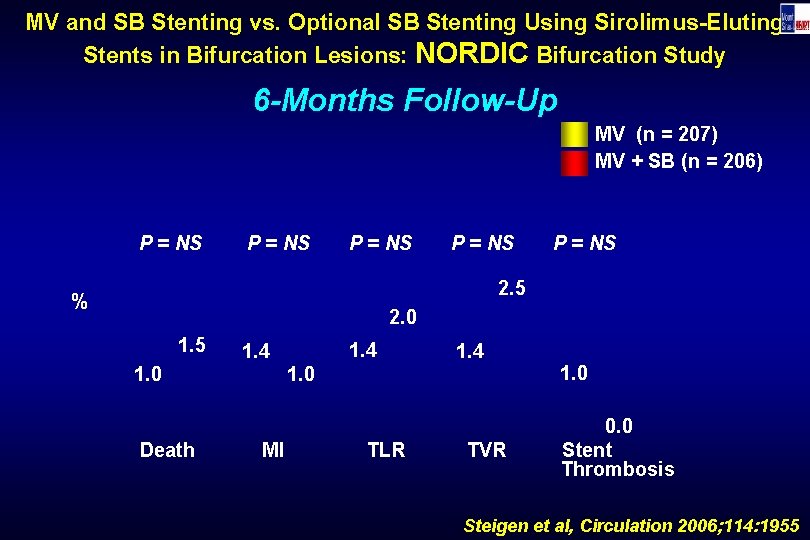

MV and SB Stenting vs. Optional SB Stenting Using Sirolimus-Eluting Stents in Bifurcation Lesions: NORDIC Bifurcation Study 6 -Months Follow-Up MV (n = 207) MV + SB (n = 206) P = NS P = NS 2. 5 % 2. 0 1. 5 1. 0 Death 1. 4 1. 0 MI TLR TVR 1. 0 0. 0 Stent Thrombosis Steigen et al, Circulation 2006; 114: 1955